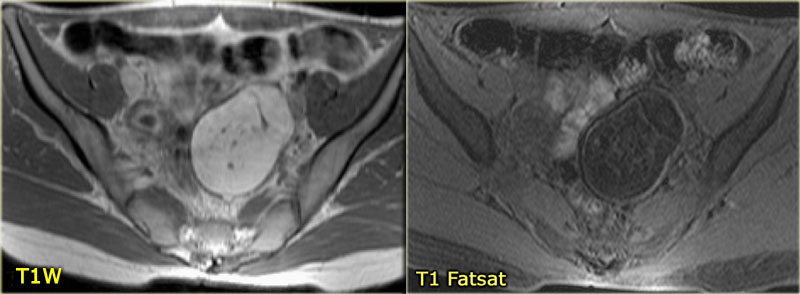

Киста яичника на кт

Киста яичника на кт 116 фото